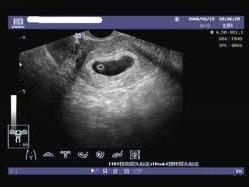

在孕早期后期或孕中期,通過B超應能檢測到胎兒心跳,如無法檢測到胎兒心跳,可能是空孕囊的征兆。

通過B超檢查發現胚胎未按照正常時間發育,如未按時出現胚芽、胎心等,可能是空孕囊的表現。

羊水是胎兒生長的重要環境,如B超檢查發現羊水過少或無羊水,可能是空孕囊的征兆。